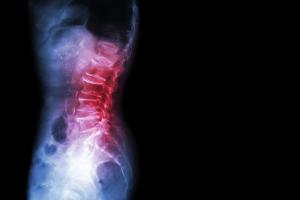

When teenaged athletes complain of lumbar back pain that worsens with activity, there should be a high index of suspicion for a spondylolysis.